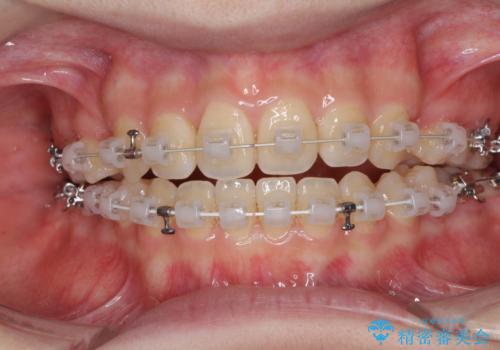

- 矯正装置

- 審美装置

- 前歯のオープンバイトを気にして来院された患者様です。

上下前歯の前後位置が大きくずれていたため、上顎左右第一小臼歯2本を抜歯してワイヤー装置による矯正治療を行うこととしました。